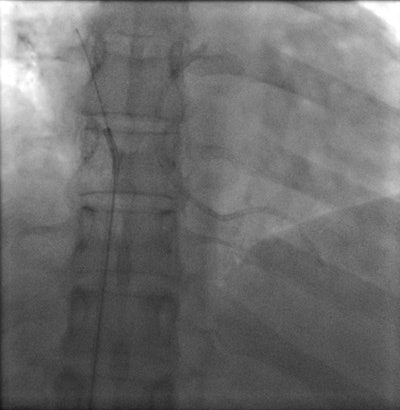

Percutaneous retrieval of the retained fragment of the fractured portacath catheter was successfully accomplished on the second attempt. Following prepping of the right groin, the right femoral vein was punctured and an 8 French sheath was inserted. Selective catheterization of the right ventricle was performed using a 6 French catheter. A 25-mm snare was used to capture the migrated retained fragment. It was then removed successfully without immediate complications.

The postoperative radiograph showed no residual fragments.

Postoperative chest radiograph.Discussion